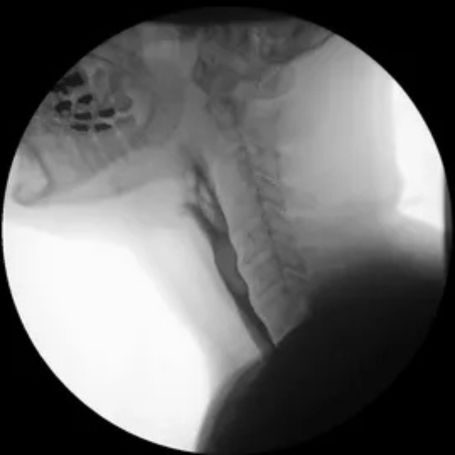

A Barium Swallow Test is a specialized X-ray examination that helps doctors visualize the upper part of the digestive system — including the throat (pharynx) and esophagus. At Diagnopein Nashik, this test is performed using advanced imaging technology to detect swallowing difficulties, blockages, ulcers, tumors, or any abnormal movements of the esophagus.

During the test, a contrast material called Barium Sulfate is swallowed by the patient. This liquid coats the inner lining of the esophagus, allowing it to appear clearly on X-ray images. The Barium Swallow study is a safe, non-invasive, and highly effective diagnostic tool to evaluate gastrointestinal disorders.

You’ll be given a barium liquid to swallow. As you swallow, X-ray images are taken in different positions. This helps visualize the movement of barium through your throat and esophagus.